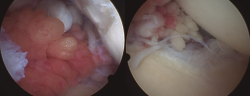

En los casos de la rodilla, con una intervención abierta (en el contexto de la colocación de una prótesis total de rodilla) y otra artroscópica, su localización fue predominantemente suprapatelar, si bien también se encontraron vellosidades (Figura 4).

Figura 4. Imágenes artroscópicas del LA en la rodilla, con presencia de vellosidades grasas en el receso suprapatelar e incluso en la zona supra- e inframeniscal.

En todos los casos se remitieron muestras de biopsia al Servicio de Anatomía Patológica (Figura 5). Se realizó, por tanto, una sinovectomía amplia y electrocauterización. En los casos de hombro en los que existía una rotura del supraespinoso suturable, se procedió a su reinserción. En un caso, ante una rotura masiva retraída, se decidió llevar a cabo una reconstrucción capsular superior. En los casos de rodilla, en un caso el desbridamiento y exéresis artroscópica fue suficiente al no existir lesiones asociadas, mientras que en el otro caso, ante la degeneración articular y la edad del paciente, se realizó un desbridamiento en el contexto de la implantación de una prótesis total de rodilla.